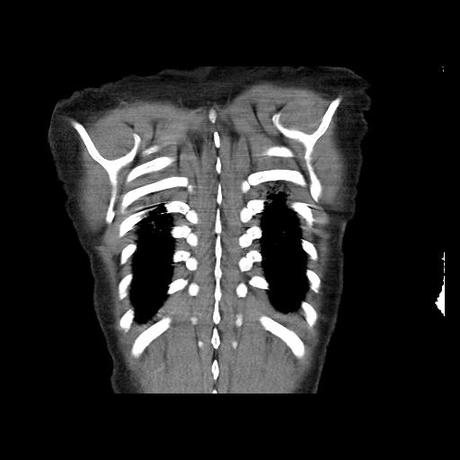

Se realiza volumen de tórax en fase simple, desde los opérculos torácicos hasta los hemidiafragmas, observándose:

El parénquima pulmonar con areas parcheadas difusas en vidrio despulido combinadas con otras areas hipodensas de baja atenuación debidas a atrapamiento aéreo y engrosamiento intersticial y zonas de fibrosis de predominio en lóbulos medios e inferiores de ambos pulmones.

- LOS HALLAZGOS PUEDEN ESTAR EN RELACIÓN A NEUMOPATIA INTERSTICIAL PROBABLE ETIOLOGIA HIPERSENSITIVA VS AUTOINMUNE/BACTERIANA/FUNGICA.